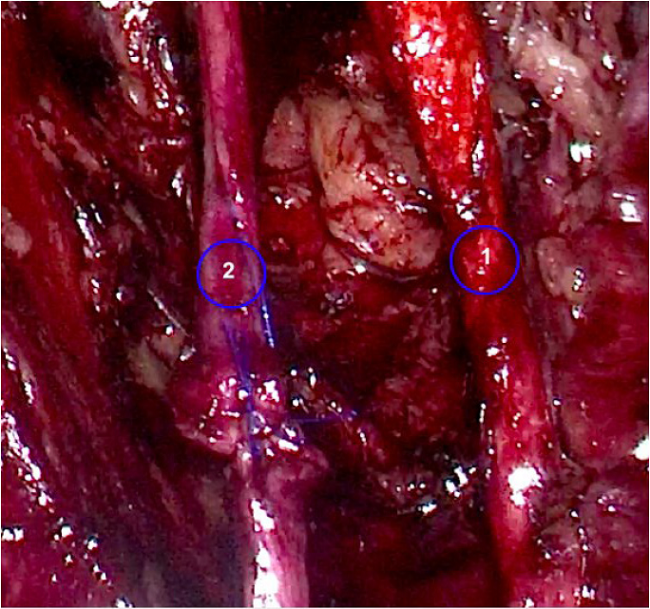

Adicionalmente, durante el procedimiento de disección del paquete ganglionar obturador izquierdo se produce una lesión completa del nervio obturador con energía bipolar avanzada (ligasure ®) que se identifica en el acto operatorio (Figura 1). Se procede a realizar una reconstrucción con neurorrafia primaria término-terminal con sutura no absorbible (prolene 5-0®) y puntos separados (Figura 2) vía laparoscópica. El reporte final de la patología informó carcinoma de células escamosas grandes no queratinizante, ulcerado, infiltrante, 5 x 8 mm de extensión horizontal, sin evidencia de invasión linfovascular, vértice y bordes libres de lesión y 43 ganglios linfáticos pélvicos negativos para compromiso tumoral. En la valoración posoperatoria, el grupo de re- habilitación indica estudios de neuroconducción y electromiografía a los 15 días del procedimiento que confirman lesión del nervio obturador izquierdo tipo axonotmesis con signos de reinervación (Figura 3). Al examen físico presenta clínica de dolor difuso en el muslo izquierdo, en cara anterior y lateral, intensidad 3-4/10 según escala análoga del dolor; en la evaluación de fuerza muscular se observa debilidad de flexores de cadera y aductores de cadera izquierdos (4/5 en la escala de fuerza muscular modificada). Presenta alteración en la velocidad de la marcha sin cambios en su patrón funcional. El estudio de electrofisiología mostró buen pronóstico dado que conservaba potencial de acción motor compuesto, reclutamiento normal y signos de reinervación, condición que orientó la estrategia de rehabilitación para optimizar la estimulación de la fibra muscular con electroterapia, además de la ejecución de ejercicios activos de aductores de cadera izquierda para lograr seguridad en la movilidad.